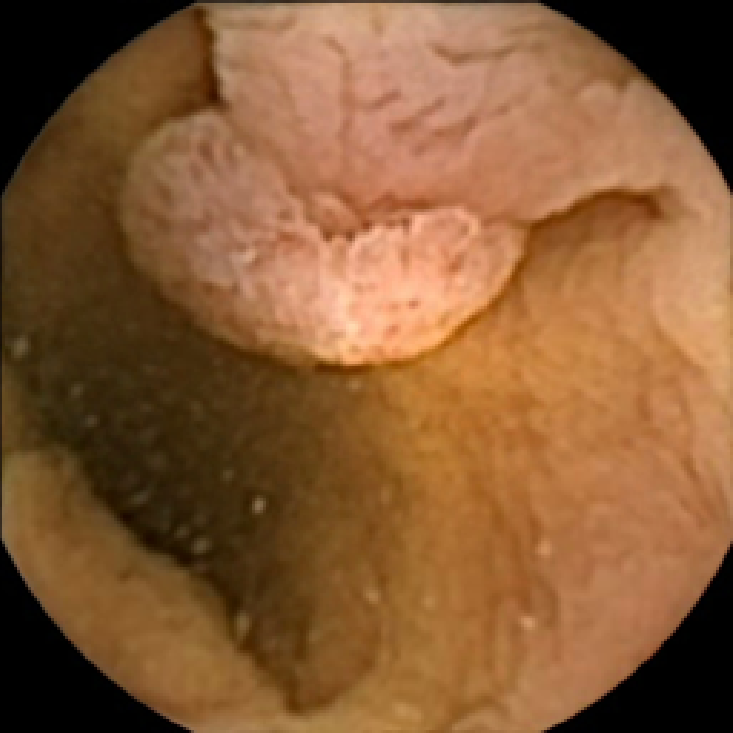

We illustrate the above considerations in Figure 4, where we compare the ellipses of inertia for a polyp frame and two frames with pronounced mucosal folds. The ellipses we plot are

| (20) |

where . The scaling term in front of is chosen so that the area of the ellipse of inertia is the same as the size of the corresponding feature.

As expected, we observe that the ellipses corresponding to mucosal folds (feature 2 in the second row and features 2 and 3 in the third row of Figure 4) are indeed much more stretched out than the ellipse corresponding to a polyp (feature 1 in the first row of Figure 4). Stretched ellipses imply higher eccentricity, thus we impose the following criterion

| (21) |

with some threshold to select moderately stretched features that are more likely to correspond to polyps.